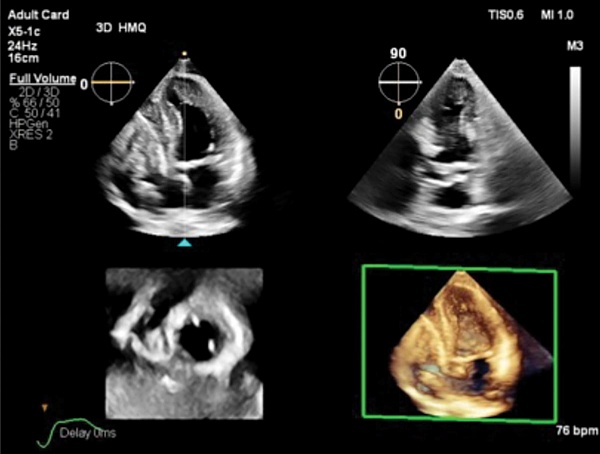

En el marco del Congreso CardioTox 2025, celebrado en Madrid, la compañía Philips ha presentado Transcend Plus, la nueva generación de sus sistemas de ultrasonido cardiovascular EPIQ CVx y Affiniti CVx. “Transcend Plus marca un hito en la calidad de imagen y la automatización mediante Inteligencia Artificial (IA)”, asegura el responsable del negocio de ultrasonido en Philips Ibérica, Sergio García.

Esta actualización ofrece avances 2D y 3D recientemente aprobados por la FDA (Agencia del Medicamento de Estados Unidos). Con 26 aplicaciones de IA integradas —la mayor cantidad del sector—, la nueva herramienta permite a los equipos de cardiología trabajar de manera más eficiente y coherente, incluso en los casos clínicos más complejos.

Además, su nueva función 2D Auto EF Advanced amplía las capacidades de análisis automático de la función ventricular izquierda, proporcionando resultados rápidos, reproducibles y fiables. “Esto se traduce en diagnósticos más precisos, menor variabilidad entre operadores y una mayor confianza clínica, tanto en laboratorios hospitalarios como en consultas ambulatorias”, señala García.